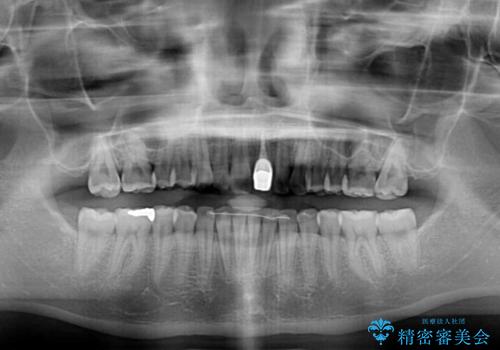

長時間のマウスピース装着と、患者様自身でのゴムかけに協力いただき、口元の突出感をしっかりと改善することができました。

前歯のオールセラミッククラウンもまるで本物の歯のように仕上がり、患者様には大変満足していただきました。